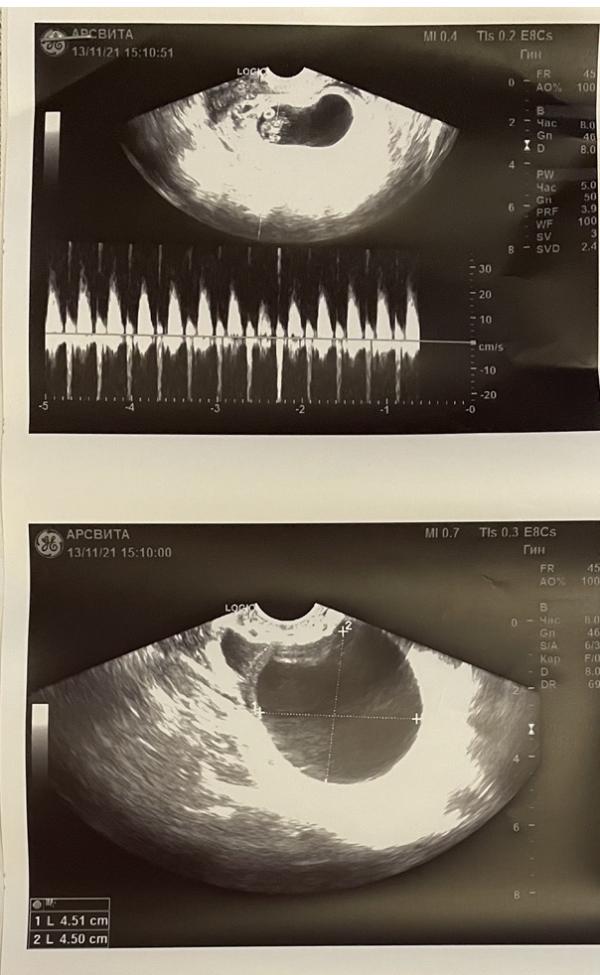

13 ноября 7 недель 4 дня, сходила на узи.

ктр до 14мм, желточный мешочек до 5мм, чсс 120уд/мин.

Гематома на месте, киста на месте, по узи 8 недель, но не в этом суть!

В головном конце эмбриона (в шее) обнаружено анэхогенное включение!… что это вообще может быть?.. начиталась ужасов, но это всё не точно же..((

Врач ничего особенного не сказала, но мне показалось, что не хотела меня пугать. Сказала, что эмбрион ещё маленький и может там всё поменяться ещё. Попросила ей потом прислать результаты скрининга.

P.S. Забежала к своей гине 15 ноября, она сказала по узи всё нормально, так развивается мозг!!! И, про врача в платной клинике, куда я ходила…Цитата: «Если она не знает и не видела такого, пуст почитает» 🙈😅 капец, что за врач попалась в платной, а я блин поверила ей 😠

Представляете, заносила сегодня мочу (прям в кабинет попросили) к Кузиной, и решила у неё спросить про узи пока она свободна. Говорит, и что вас смущает? Отвечаю, что вот это анэхогенное включение.. А она говорит, что это нормально, так развивается мозг эмбриона!!! И если та гинеколог узист из платной первый раз такое видит, то пусть почитает…это Кузина сказала 😅 блин, я вот думаю, неужели в платной эта гинеколог и врач узд со стажем 25 лет! -«двоечница»??? Или что 🙈🙈🙈 пипец !